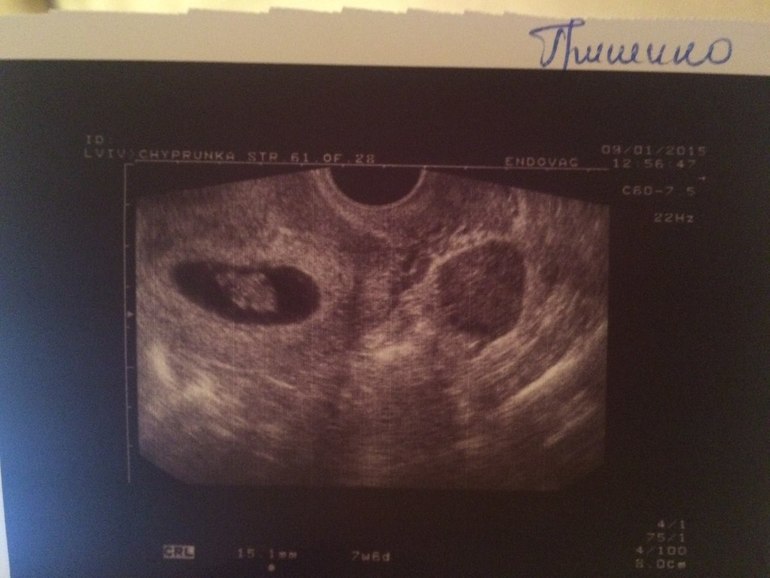

А вот и наше фото)